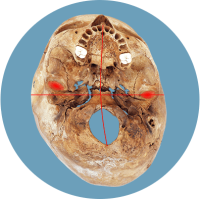

Das größte Problem besteht darin, dass der Kopf in seiner Struktur verändert wird – die Schädelbasis wird schief. Davon sind hauptsächlich die Stellung der Ohren (Gleichgewichtsorgane), die Kiefergelenke (Zahnfehlstellungen) und Halswirbelkörper betroffen. Kritisch wird dies spätestens, wenn sich die Kinder zum Ende des 1. Lebensjahres aufrichten und eine schiefe Wirbelsäulenhaltung entwickeln.

Die verschobene Position der Gleichgewichtsorgane ist durch die roten Kreuze gekennzeichnet.

Fehlerhafte Informationen aus den verschobenen Gleichgewichtsorganen bzw. dem Nackenrezeptorenfeld beeinflussen die Verarbeitung im Gehirn und können zu einer Fehlhaltung der Wirbelsäule führen.